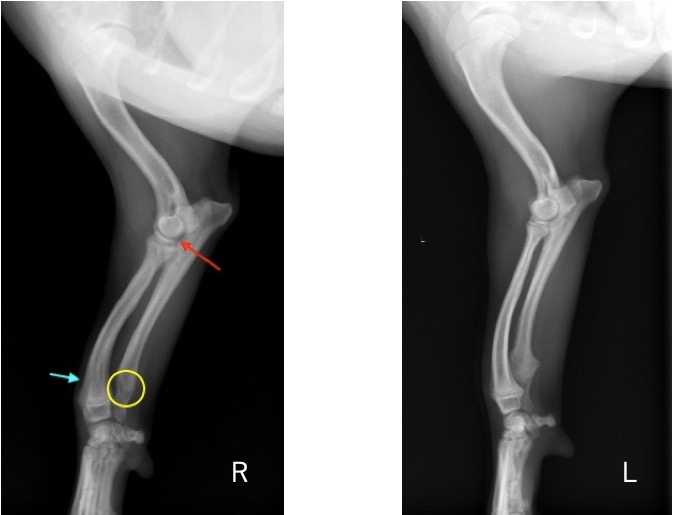

単純X線画像検査において、右側の尺骨遠位成長板領域の不透過性亢進、橈骨の頭側湾曲、鈎状突起と上腕骨顆の間隙が広がっている所見が認められたため、尺骨遠位成長板早期閉鎖が疑われました。

前腕のLateral像 (黄丸;尺骨遠位成長板の不透過性亢進 青矢印:橈骨の湾曲 赤矢印:鈎状突起と上腕骨顆の間隙)

前腕のAP像 (黄丸:尺骨遠位成長板の不透過性亢進 青矢印:橈骨の湾曲)